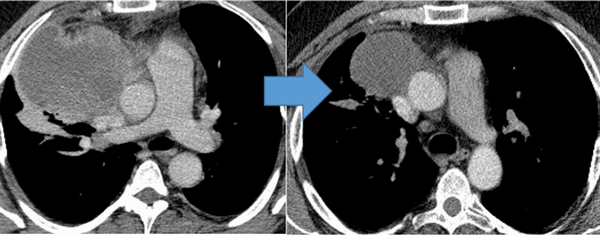

Рисунок 6. — КТ органов грудной клетки - семинома средостения.

Гистологическая картина новообразования в основном смешанного происхождения, имеет тератоидный компонент и клетки, которые характерны для новообразования желточного мешка.

Герминогенные опухоли средостения, как правило, локализуются за грудиной. Для доброкачественных новообразований (тератом) характерен медленный рост, для злокачественных (тератобластом и других неоплазий) - агрессивное распространение и быстрое прорастание близлежащих органов. Наиболее частыми проявлениями герминогенной опухоли являются одышка, кашель и боли в груди. При сдавлении верхней полой вены возникают шум в голове, головная боль, шум в ушах, расстройства сознания, сонливость и нарушения зрения. Возможны судороги. При злокачественных герминогенных опухолях наблюдаются гипертермия, лихорадка, снижение веса и нарушения функций различных органов, обусловленные прорастанием либо отдаленным метастазированием.

Показания к химиотерапии определяются степенью распространенности процесса, наличием легочных/внелегочных метастазов. Стандартным режимом химиотерапии при герминогенных опухолях является режим «BEP», включающий блеомицин, этопозид и цисплатин. Для пациентов с дыхательной недостаточностью, обширным поражением легких, во избежание легочной блеомициновой токсичности, как альтернативный вариант, может быть использованы режимы химиотерапии VIP (этопозид, ифосфамид, цисплатин) или ЕР (этопозид, цисплатин).

Для оценки эффективности химиотерапии каждые 2 цикла и после ее окончания проводится компьютерная томография исходных зон поражения, перед каждым циклом мониторинг уровня опухолевых маркеров. Рост маркеров на фоне лечения или после его завершения, а также замедление их снижения свидетельствует об активности опухолевого процесса и необходимости проведения второй линии химиотерапии.

![Герминогенная опухоль средостения до лечения и после 4х циклов химиотерапии по схеме «ВЕР » - уменьшение опухоли более чем на 50% (КТ грудной клетки).]()

Герминогенная опухоль средостения до лечения и после 4х циклов химиотерапии по схеме «ВЕР » — уменьшение опухоли более чем на 50% (КТ грудной клетки)